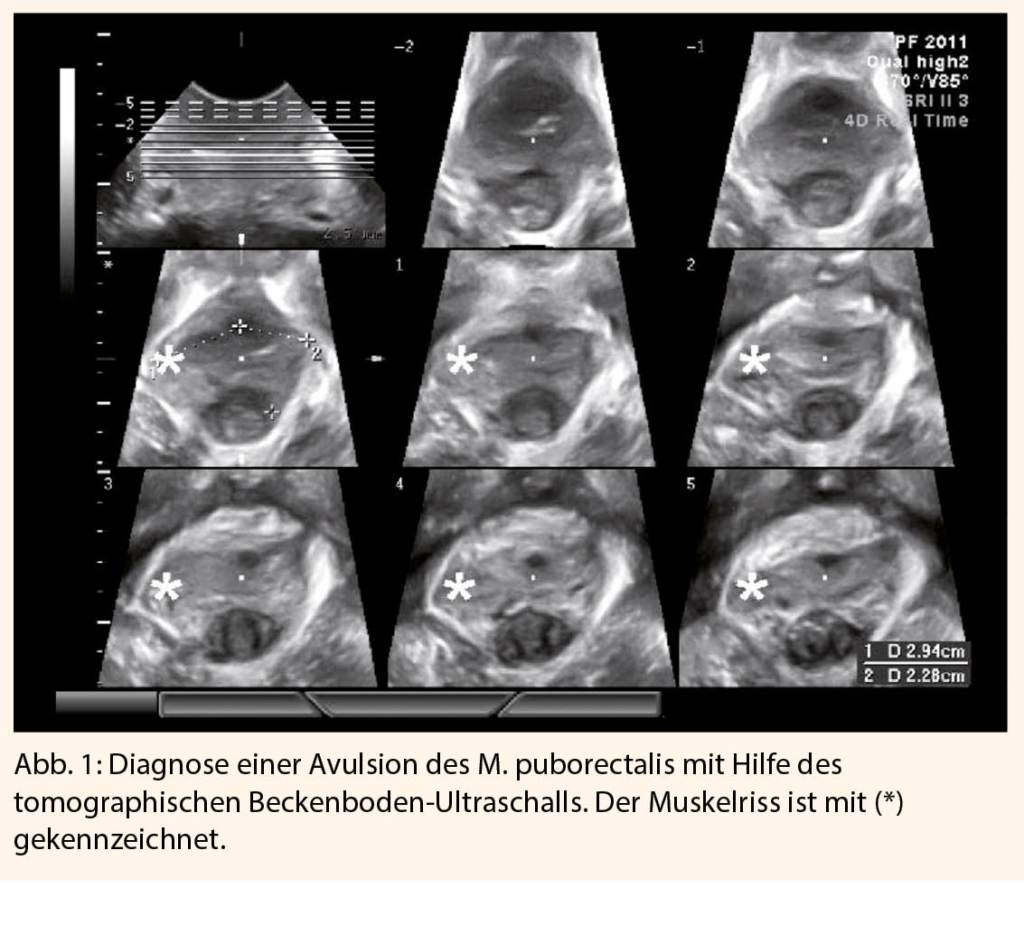

Die Identifikation und Behandlung von Dammrissen Grad III-IV ist ein Schwerpunkt der geburtshilflichen Ausbildung. «In den letzten 10 Jahren ist jedoch klar geworden, dass der Begriff Beckenbodentrauma eine zusätzliche Kategorie von Verletzungen umfasst, die meist verborgen bleiben und nur selten unter der Geburt diagnostiziert werden», so der Referent. Fortschritte in der bildgebenden Diagnostik, insbesondere in der Kernspin- und 3-D-/4-D-Ultraschalldiagnostik, ermöglichen dem Geburtshelfer heute die routinemässige Darstellung des M. levator ani, vor allem des M. puborectalis (Abb. 1). Es ist inzwischen klar, dass das Puborectalis-Trauma recht häufig ist und Avulsionen bei bis zu 30% aller vaginalen Geburten vorkommen. «Dies könnte der numerisch wichtigste Faktor in der Pathogenese von Prolapsbeschwerden sein und damit der wichtigste modifizierbare Risikofaktor», folgerte Prof. Dietz.

Die Abteilung von Prof. Dietz in Sydney hat in den letzten 15 Jahren tomographische Ultraschallverfahren zur Beurteilung solcher Schäden entwickelt, welche zunehmend globale Verbreitung erfahren (Abb. 1 und 2).